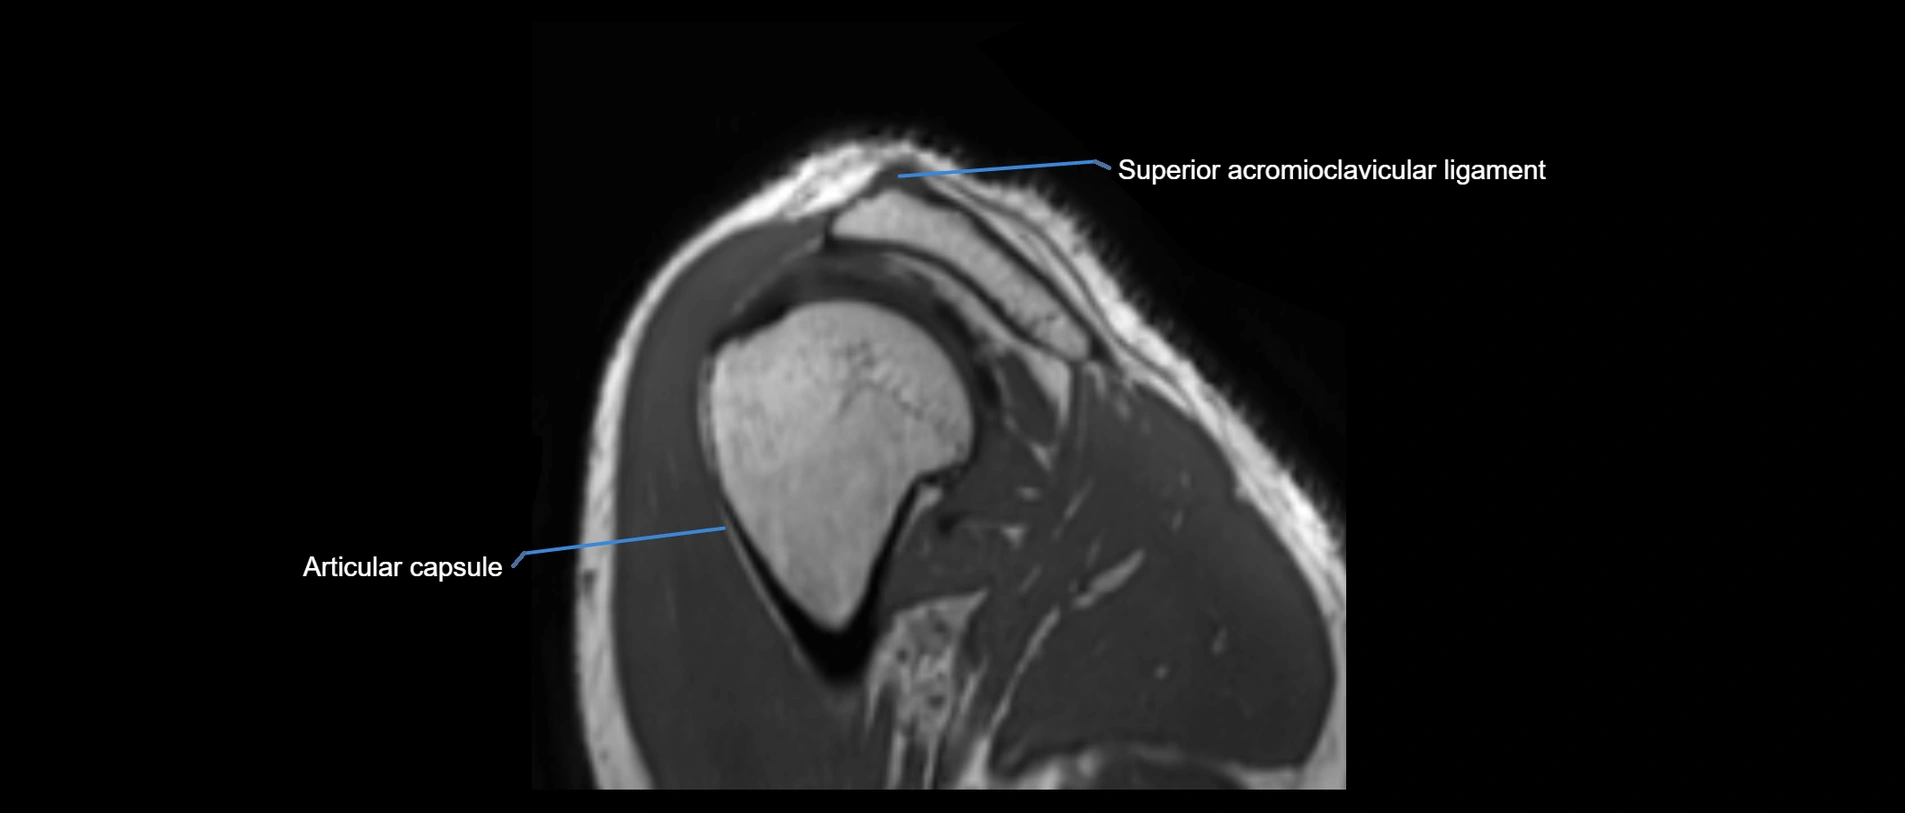

MRI images

image

MRI Appearance

• T1-weighted images:

• Normal ligament: Low signal (dark linear band) spanning acromion to clavicle.

• Surrounding fat planes: Bright, delineating the ligament clearly.

• Marrow of clavicle and acromion: Bright due to fatty content.

• Tears: Discontinuity or irregular thickening with intermediate-to-bright signal.

• Chronic injury: Thinning, fraying, or irregular low-signal fibers with adjacent scarring.

• T2-weighted images:

• Normal ligament: Low signal, homogeneous.

• Partial tear or sprain: Focal hyperintensity or thickening.

• Complete tear: Discontinuity with fluid-bright gap between clavicle and acromion.

• Associated edema: Bright signal in distal clavicle or acromion marrow.

• STIR:

• Normal ligament: Dark linear band.

• Injury or inflammation: Bright hyperintense signal in and around ligament fibers.

• Highlights periligamentous soft-tissue edema, especially in acute trauma.

• Proton Density Fat-Saturated (PD FS):

• Normal ligament: Low signal, uniform thickness.

• Partial tear or sprain: Bright signal or contour irregularity.

• Complete tear: Clear discontinuity with bright signal gap and joint effusion.

• Excellent for assessing joint capsule, coracoclavicular ligaments, and periarticular edema.